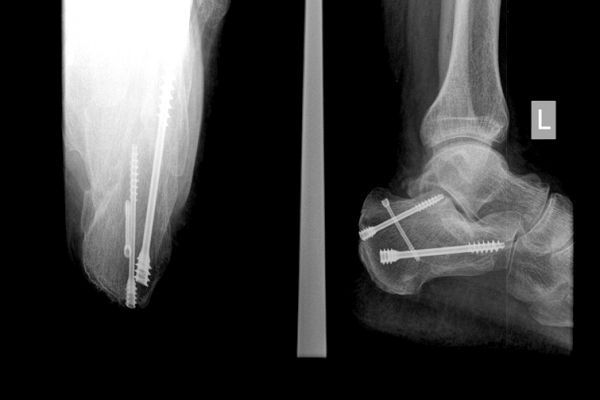

Gabinet ortopedyczny prowadzony przeze mnie specjalizuje się w leczeniu schorzeń i urazów kończyn górnych i dolnych. Zajmuję się leczeniem choroby zwyrodnieniowej stawu biodrowego i kolanowego, uszkodzeń wewnętrznych stawu kolanowego i barkowego, złamań w obrębie kończyn górnych i dolnych oraz urazów ścięgien i mięśni kończyn górnych i dolnych. Ponadto wykonuję diagnostykę USG narządu ruchu i badanie preluksacyjne (USG bioderek niemowląt). Leczę również neuropatie uciskowe kończyn (zespół kanału nadgarstka, rowka nerwu łokciowego, kanału Guyona) oraz uszkodzenia wewnętrzne stawów kończyn górnych i dolnych. Zapraszam do mojego gabinetu, gdzie dobiorę odpowiednie do schorzenia metody leczenia i zakwalifikuję do ewentualnego leczenia operacyjnego. W celu umówienia się na wizytę proszę o kontakt telefoniczny z rejestracją gabinetu ortopedycznego w Lesznie.